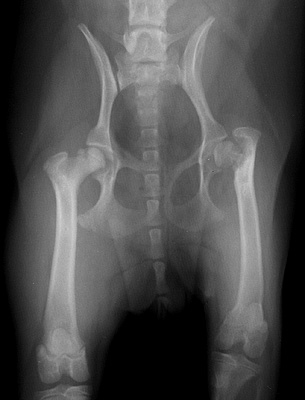

Radiograph of the Ventrodorsal view

Figure 1: Ventrodorsal view